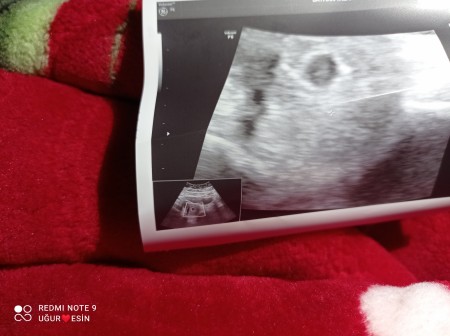

Sizce kaç haftalik

Kizlar sizce kaç haftalık

gebelik

6 haftalık mı benim o haftada böyleydi

Peki ne zaman bebeği gördüğünüz şuan benim sadece kese

Canım ben ilk doktora gittiğimde 6 haftalıktı kese görünüyordu ama bebek gözükmüyordu 8 haftalıkken gördük tam olarak :)